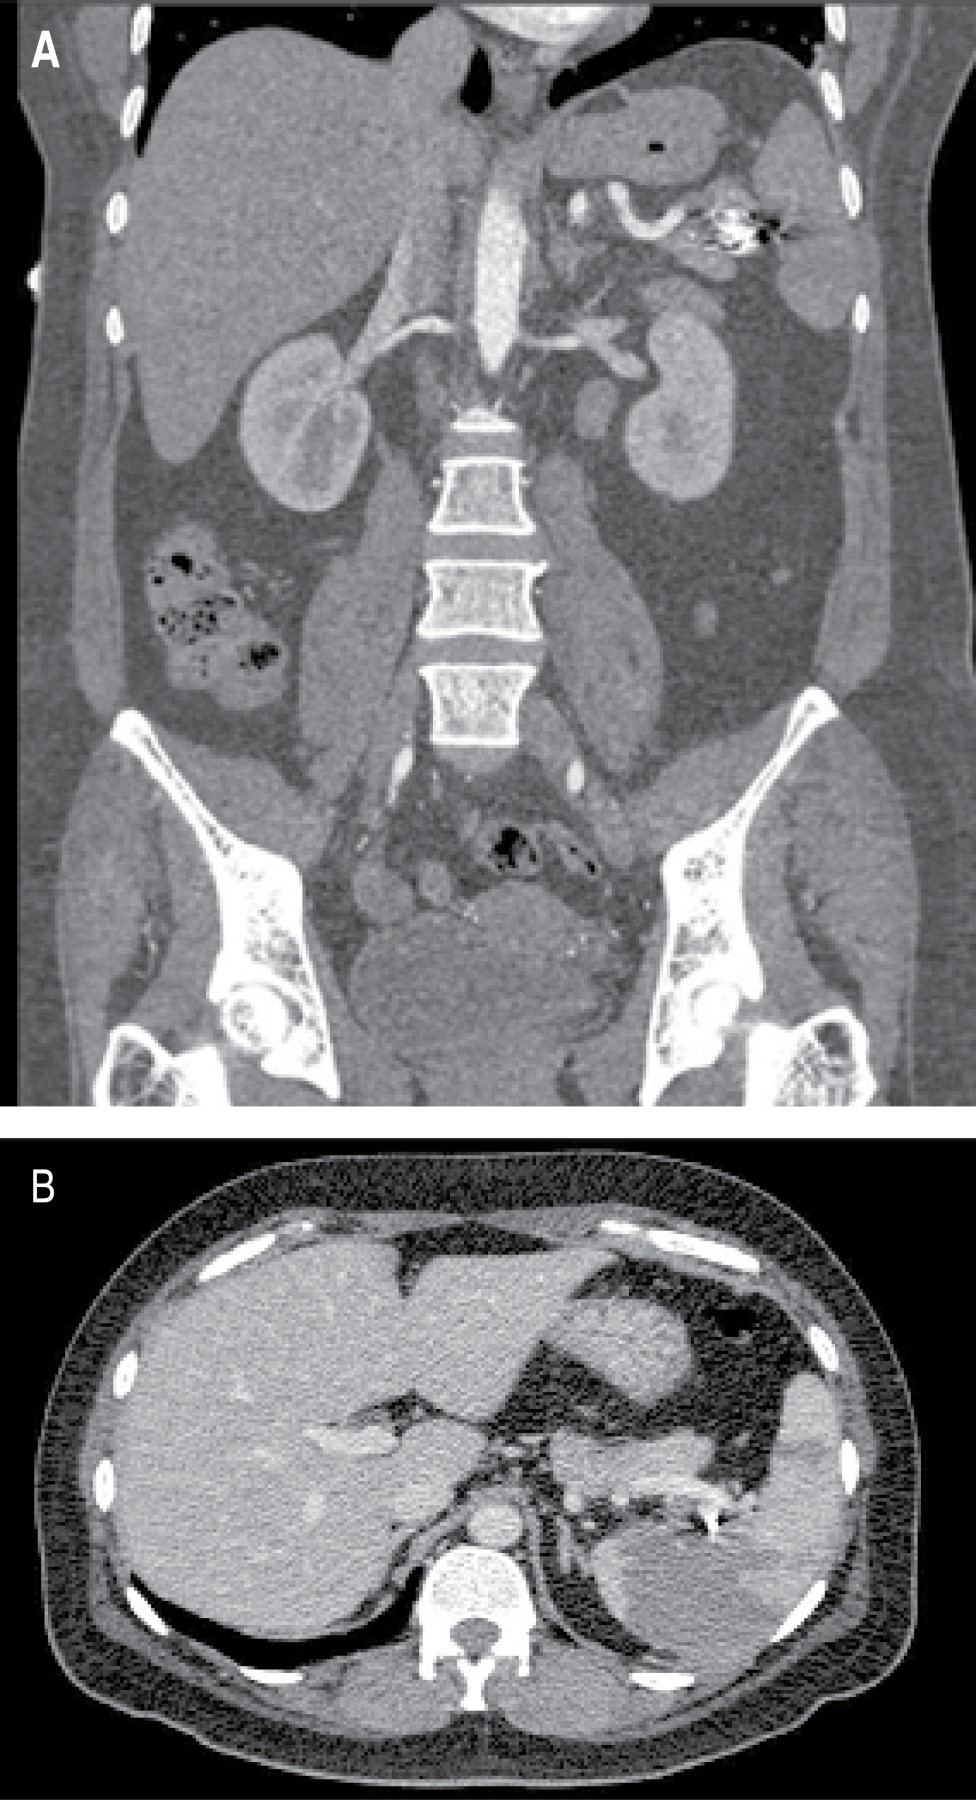

This was a 41-years old female patient with a history of hypothyroidism diagnosed at 21 years old, currently without medical treatment for 40 years old due to apparent control, diagnosis of uterine myomatosis at 40 years old, without treatment; history of two cesarean sections, being the last one at 23 years old, without complications. She suffered a car accident with rollover at age 40, without apparent organic damage. She began her current condition after a car accident one year earlier with intermittent, stabbing, non-radiating pain in the left hypochondrium, with no aggravating or extenuating factors; on physical examination, she presented pain in the left hypochondrium on deep palpation, with no other pathological findings. Ultrasound was performed with results compatible with an aneurysm of the splenic artery and cholelithiasis; the diagnostic approach was complemented with angio-tomography of the abdominal aorta finding a splenic artery of standard caliber, with focal saccular dilatation in distal segment compatible with an aneurysm of 17.7 × 15.9 mm and neck of 5.5 mm, with mural thrombus of 2 mm, with no signs of rupture; vesicular lithiasis and uterine myomatosis were also seen. With no apparent complications, selective embolization with coil placement was performed in conjunction with angiology (Figure 1). In the immediate follow-up, the patient presented abdominal pain and leukocytosis; a new angio-tomography was performed with data suggestive of splenic artery occlusion and splenic infarction (Figure 2). Due to the findings mentioned above, it was decided to perform splenectomy and conventional cholecystectomy using a surgical approach with a midline supraumbilical incision, with the following findings: Thin-walled gallbladder, multiple calculi inside of 5-10 mm approximately, cystic artery of 2 mm, cystic duct of 3 mm, spleen of 13 × 10 cm approximately, with multiple ischemic areas, an aneurysm of the splenic artery at the level of the splenic hilum, posterior to its bifurcation (Figure 3). The postoperative course was without complications, so she was discharged three days after surgery and received the corresponding vaccination for patients with splenectomy. The histopathological report included findings of splenic artery aneurysm with atherosclerosis, splenic parenchyma with congestive vessels, and chronic calculous cholecystitis.

Although the literature mentions that only 20% of patients with splenic aneurysms have symptoms, the presence of pain in the left hypochondrium of a long evolution led to requests for complementary studies in this patient. An ultrasound was performed as an initial approach, reporting findings compatible with splenic artery aneurysm and cholelithiasis, so, following the study protocol mentioned in the literature, we proceeded to perform an angio-tomography of the abdominal aorta to have a complete picture of the case, visualize the size and location of the lesion and its relationships and thus properly the therapeutic plan.

Figure 2